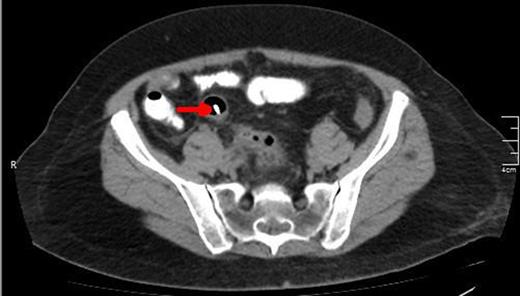

A lower CT view of the same patient showing the stent (red arrow).